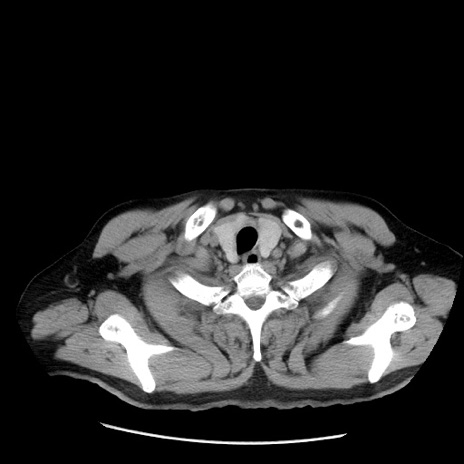

症例20(横断像)

【症例】 60歳代男性

【主訴】 腹部膨満、嘔吐

【現病歴】5日前頃より倦怠感を認め食事量減少し4日前の朝嘔吐、食事摂取困難となった。 3日前近医受診し点滴施行され整腸剤などを処方された。 当日他院を受診し、腹部膨満著明、炎症反応の上昇(CRP10.8、WBC11200)あり、紹介受診となる。

【既往歴】 躁うつ病(抗精神病薬多数内服あり)

【身体所見】 意識JCS1 受け答えがはっきりしないBP 111/57mHg、 P 67bpm、、BT35.2°C、SpO2 97%(RA)、 腹部:膨隆、打診で鼓音あり、全体的に圧痛有り、腸蠕動音(-)、反跳痛ははっきりせず。

【データ】WBC 11400、CRP 14.20